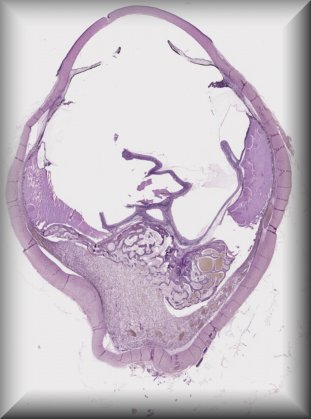

Alexandre Moulin (Laussane): Pigmented ciliary body mass in a 35 yo male. |